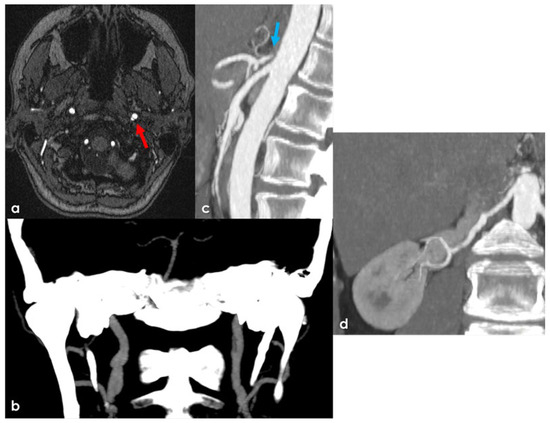

Background: Heterozygosity for pathogenic variants in the ABCC6 gene has been associated with an increased incidence of cerebrovascular diseases. This study aims to characterize the prevalence and clinical and neuroradiological phenotypes associated with monoallelic and biallelic ABCC6 variants in pediatric and adult patients presenting with arterial ischemic stroke or cerebral small vessel disease (CSVD). Methods: We conducted a retrospective observational study on 143 consecutive patients (48 pediatric, 24 juvenile, 71 adult) diagnosed with ischemic stroke or CSVD of unknown etiology. Clinical and neuroradiological data were collected and analyzed in relation to the identified genetic variants through next-generation sequencing. Results: Among the patients, 16 (11.2%) tested positive for causative variants in the ABCC6 gene, with 11 subjects carrying monoallelic variants and 5 carrying biallelic variants. Patients with biallelic variants exhibited severe and complex vasculopathy, with a high incidence of early ischemic events. In contrast, monoallelic carriers predominantly presented with microvascular disease manifestations, including lacunar strokes and signs of CSVD. Conclusions: The results suggest a significant age-dependent phenotypic divergence in patients with ABCC6 variants, highlighting the impact of heterozygosity on cerebrovascular health. Identifying these variants may enhance risk stratification and inform management strategies in patients with traditional vascular risk factors. Full article